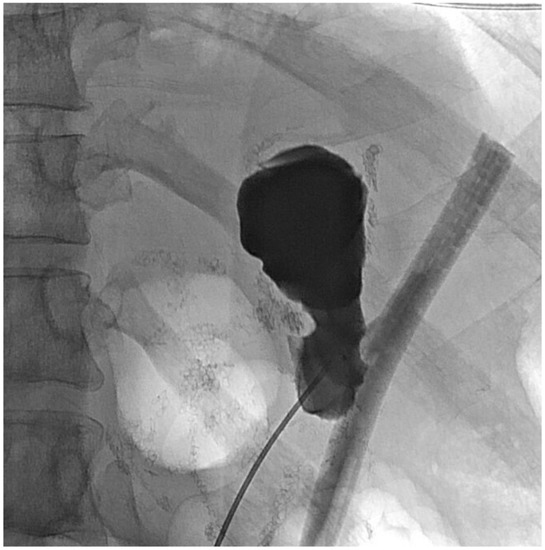

2. Detailed Case Description